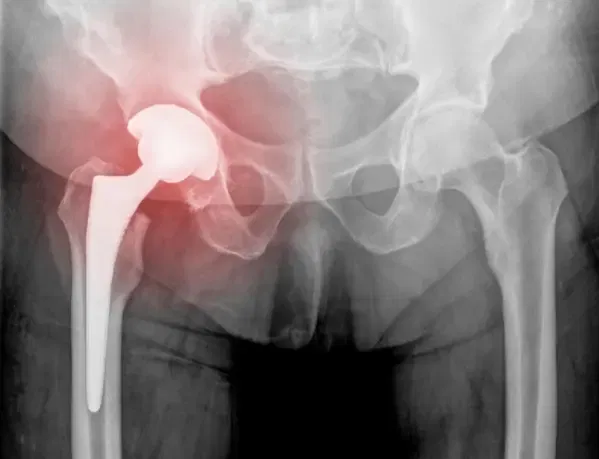

Tige fémorale

L’image ci-dessus montre un composant fémoral à revêtement poreux utilisé dans les opérations de révision de la hanche. Le revêtement entièrement poreux assure une croissance biologique de l’os et une fixation solide. Grâce aux progrès des techniques chirurgicales et des implants, les prothèses de hanche primaires durent généralement 20 ans ou plus.